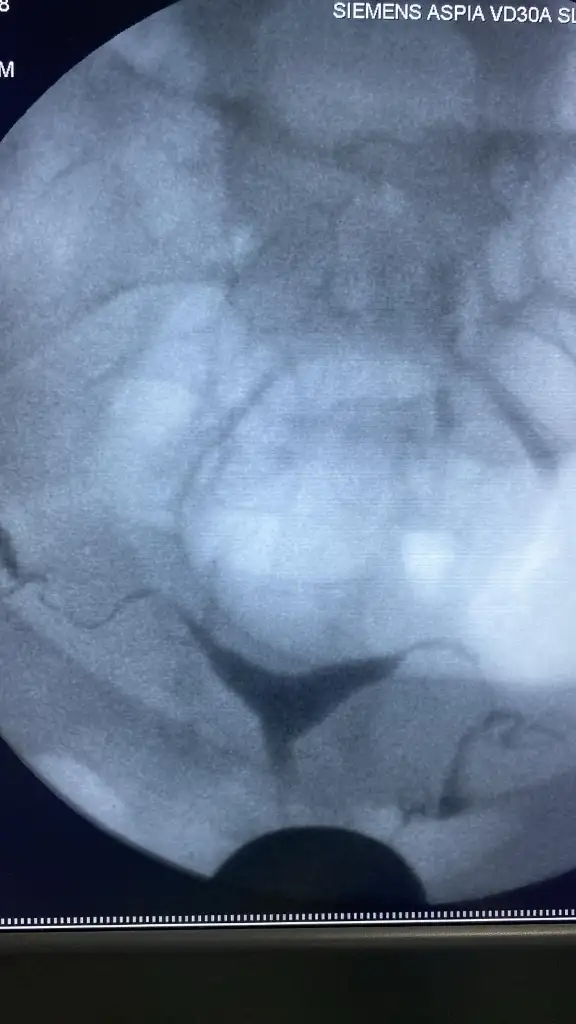

Benim sonuçlarım böyle.

Rica etsem hsg raporunuzu da koyar mısınız? Sizin ve kendi rahim şeklimi chat gbt ye yükledim. Sizin rahminizde yapışıklık olduğunu iddia etti. Sizden istemememin sebebi acaba benimde gerçekten histereskopiye ihtiyacım var mı bunu merak ediyorum

Benim bir raporum yok e nabıza baktım da sadece görüntü var

Bende kendi kullandığım uygulamada sordum herhangi bir problem olmadığını söyledi. Aynı program yani sizinkilyle